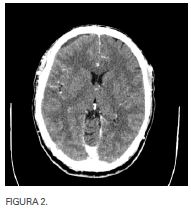

Se decide realizar cirugía urgente con unciformectomía, meatotomía media, etmoidectomía anterior, acceso a ambos recesos frontales con cultivo de contenido purulento de seno frontal derecho por vía endoscópica; por parte de neurocirugía actitud expectante. Tras mejoría clínica inicial y a pesar de no llevar taponamiento nasal, a las 32 horas presenta aumento de la cefalea frontal, así como occipital por lo que se realiza estudio radiológico urgente (figuras 3, 4 y 5). En el mismo se demuestra correcta aireación de seno frontal derecho así como progresión de empiema epidural con  componente subdural hacia convexidad derecha, desplazamiento de la línea media, paquimeningitis y cerebritis adyacentes. Pese a la gravedad de las imágenes el paciente no presenta focalidad neurológica y tiene una puntuación de 15 en la escala de coma de Glasgow.

En este momento se realiza craneotomía derecha para evacuación del contenido purulento intracraneal. También se realiza nueva exploración endoscópica, no apreciando solución de continuidad

entre el espacio epidural y el seno frontal derechos.